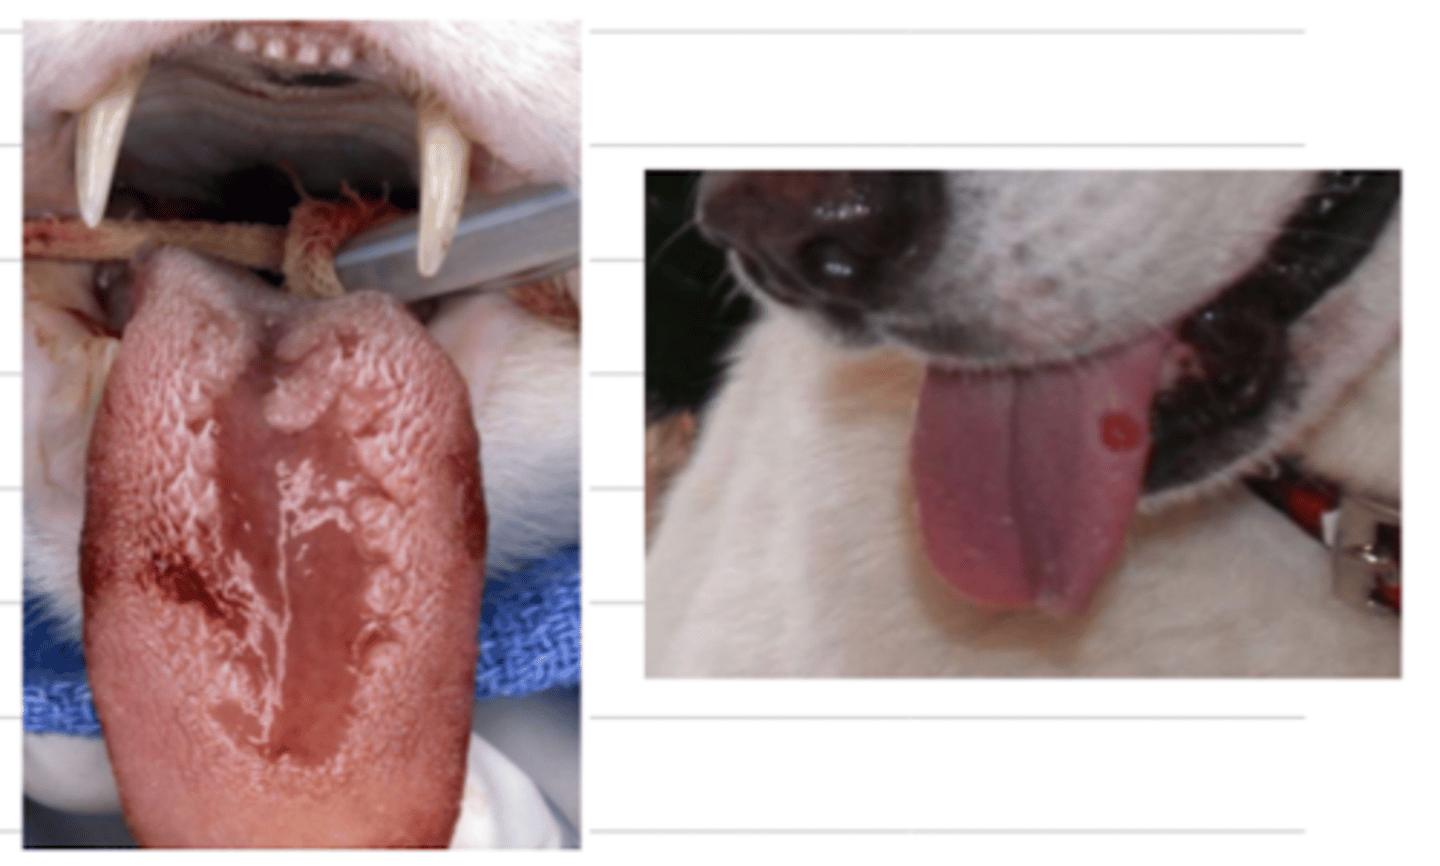

glossitis

what is the medical term for this issue?

what might be possible etiologies of glossitis?

pine processionary caterpillars- dogs commonly lick them, and they damage their oral cavity, commonly causing glossitis

what are these? what problem do they commonly cause in the animal?